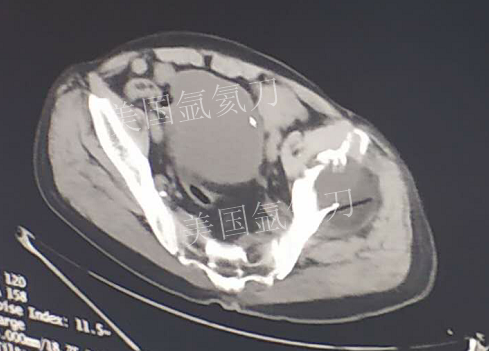

73岁臀部氩氦刀冷冻消融

发布人:美国氩氦刀技术官方网站    发布时间:2019/2/21 13:51:52